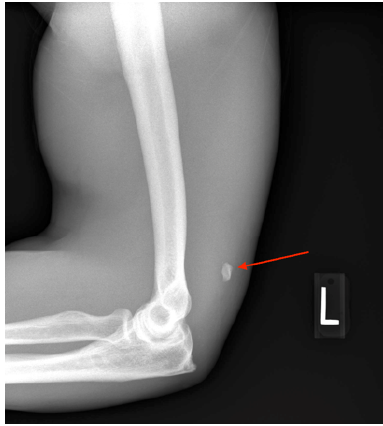

Case Report

A Case of Bilateral and Simultaneous Triceps Tendon Rupture in a 42-Year-Old Male Bodybuilder

Kacie L Mitchell, Eiline Cai and Colten Luedke. 6(3): 08-13.